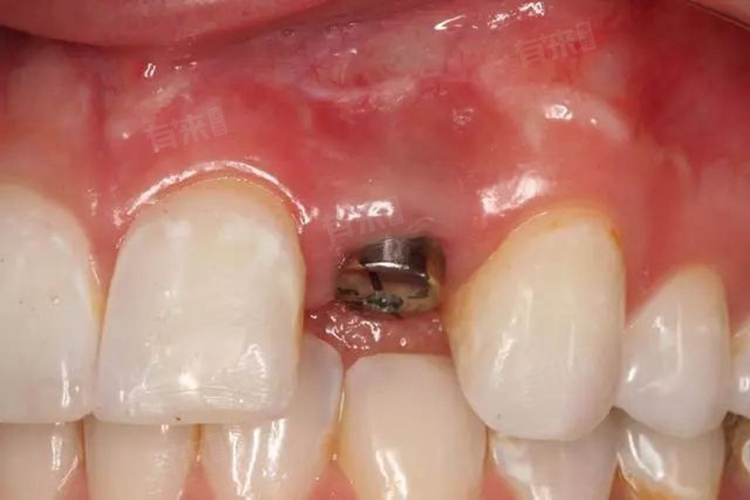

- 安装愈合基台:清理完种植体表面后,卸掉覆盖螺丝,再使用旋转刀及小剥离子清除表面的骨组织。根据黏膜的厚度和穿龈高度与对颌牙的咬合距离,选择合适的愈合基台,将底部六边形孔对准种植体上端六边形,旋紧基台固定螺丝。随后旋入愈合螺丝帽,确保基台稳固。